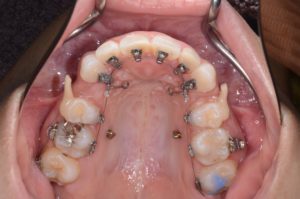

Q6. 裏側矯正(舌側矯正)の特徴は?

A. 装置が見えにくい反面、高度な技術が必要です。

裏側矯正は審美性に優れていますが、発音への影響や装置調整の難しさがあります。

そのため、十分な経験を持つ歯科医師による治療が重要とされています。